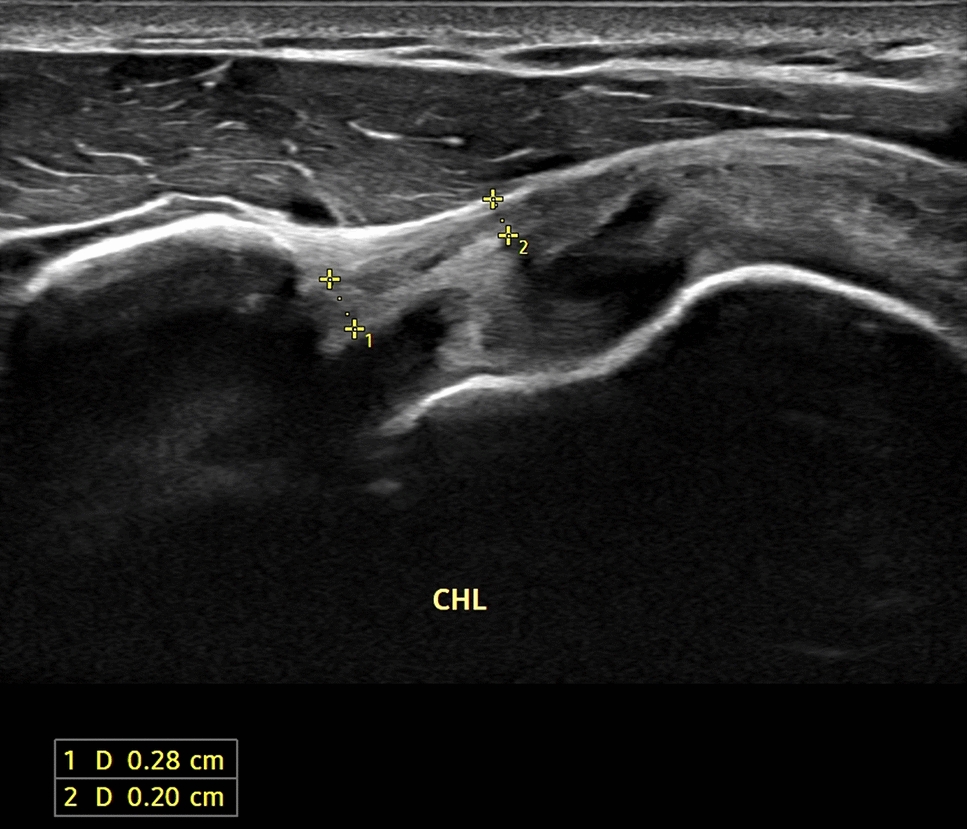

Ultrasound-guided preoperative skin-marking for deep inferior epigastric perforator flap surgery dlvr.it/TDdS6b